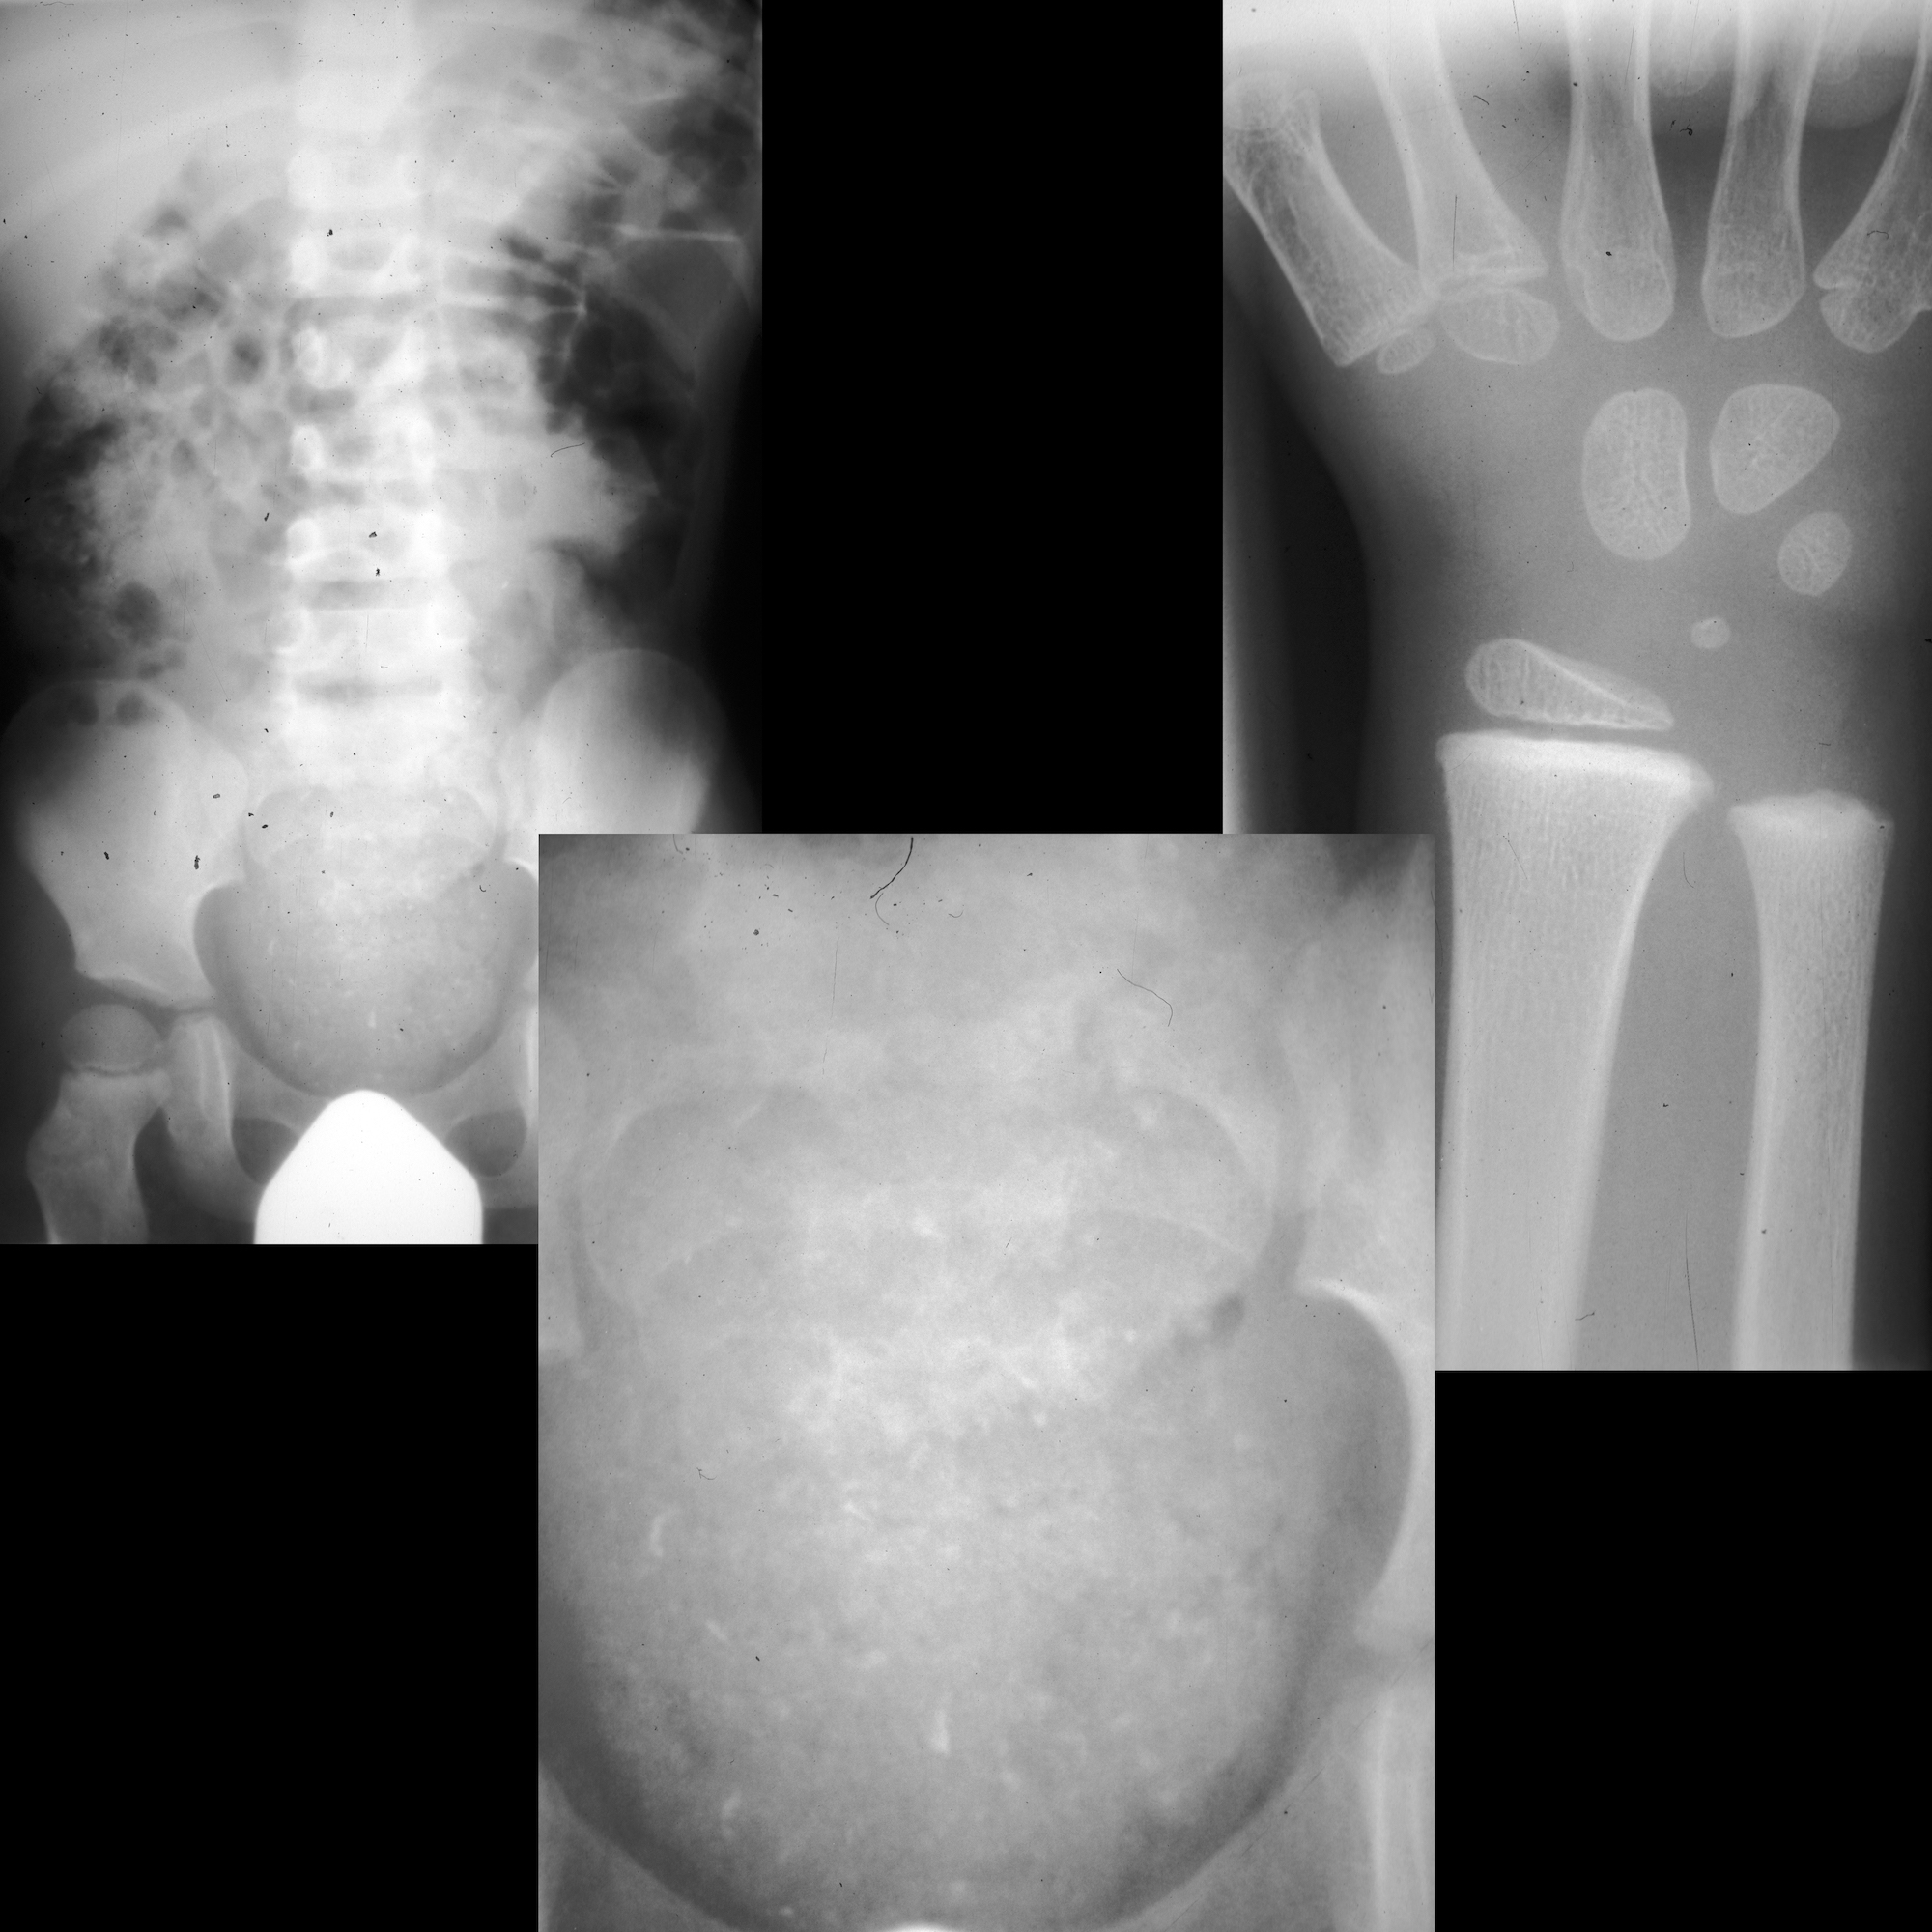

Lead Poisoning Pediatric Radiology Reference Article Pediatric X Ray Lead Exposure A patient’s blood lead level (bll) is measured in micrograms of lead per deciliter of blood (μg/dl). Main source of lead intoxication is lead paint used in houses painted before 1980; Always search for lead lines in any child with an ingested foreign body; Radiation protection apparel (rpa) is used during diagnostic imaging and interventional procedures to minimise incidental radiation. X Ray Lead Exposure.

Learning Radiology Lead, poisoning, plumbism, intoxication, ingestion X Ray Lead Exposure Always search for lead lines in any child with an ingested foreign body; Thyroid shield can decrease the amount of effective dose by 2.5 fold and almost 50% reduction in total exposure. Cdc recommends testing blood for lead exposure. Radiation protection apparel (rpa) is used during diagnostic imaging and interventional procedures to minimise incidental radiation exposure. Main source of lead. X Ray Lead Exposure.

Abdominal radiograph demonstrating several radiopaque densities X Ray Lead Exposure Describe guidelines for blood lead screening and confirmatory diagnostic testing on patients at risk of recent or ongoing lead exposure, and describe imaging and other clinical modalities. Thyroid shield can decrease the amount of effective dose by 2.5 fold and almost 50% reduction in total exposure. Always search for lead lines in any child with an ingested foreign body; A. X Ray Lead Exposure.